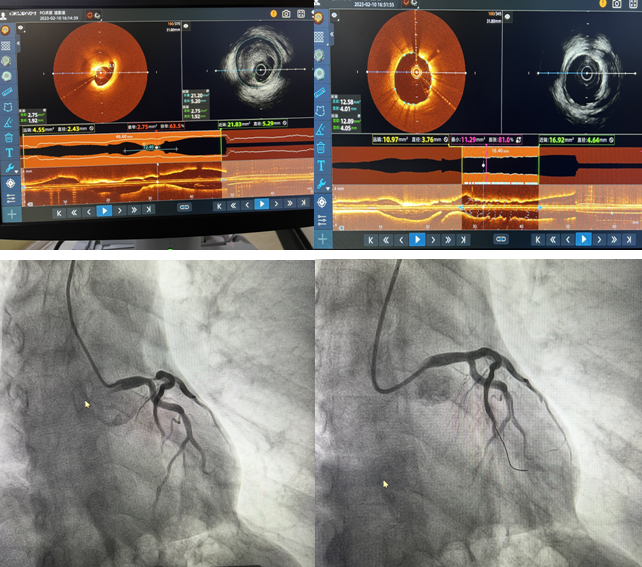

2月10日,我院心內二科主任郭明帶領的心臟介入團隊成功完成棗莊市首例IVUS-OCT雙模一體機全程指導PCI手術,標志著我院冠脈介入技術“精準化”又向前邁進了一大步。

患者,男,71歲,因“發(fā)作性胸痛5天”住院,肌鈣蛋白陽性,胸導聯(lián)T波倒置,臨床診斷為急性冠脈綜合征。冠脈造影檢查示:左前降支開口至左主干重度狹窄達90%,并累及對角支開口狹窄達80%。患者左主干及前降支開口同時存在嚴重狹窄,狹窄嚴重且存在不穩(wěn)定斑塊,需更加精準支架定位與覆蓋病變,要保證支架的貼壁絕對良好,此處一旦形成亞急性血栓極有可能引起患者猝死,單純的冠脈影像并不能完全達到此種理想的指導作用。經過與患者家屬溝通,郭明主任和楊大成副主任組織團隊人員討論后,決定應用IVUS-OCT雙模一體機全程指導下實施病變血管介入手術。介入科李紅衛(wèi)主任及盧慶林副主任進行圖像采集及分析解讀,確定冠脈內斑塊性質,精準判定血管直徑、病變長度和支架落腳點,指導選擇合適型號的支架,術后再次應用IVUS-OCT雙模一體機,觀察支架貼壁及膨脹良好,支架兩端無夾層,手術取得成功。

近年來如何進行優(yōu)化的介入治療成為當前心血管領域的熱點。單純冠脈造影無論在定性診斷還是定量診斷上,都存在一定的局限性。IVUS具有更深的成像深度,但空間分辨率差;OCT具有更好的分辨率,能更好地對比斑塊成分,但其成像穿透深度有限。因此,單一的IVUS或OCT很難完全提供血管及斑塊內部完整的解剖學信息。IVUS-OCT一體機是集光學成像、聲學成像、硬件和軟件于一體的新型血管內成像技術,實現(xiàn)了利用一根導管、一次掃描成像就可以完成兩項血管內影像檢查,是精準PCI技術的進一步提升。